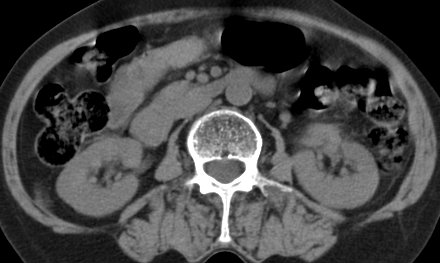

以下是引用齐原在2006-11-8 23:21:00的发言:[br]肝脏体积增大.肝表凸凹不平,肝内胆管扩张,胆总管扩张,胆总管末端突然截断,胰腺勾突增大,形态不规则.胰管扩张.考虑胰头癌.并低位梗阻性胆系扩张,胆囊炎.脾大.建议增强

以下是引用dyqct在2006-11-9 9:14:00的发言:[br]肝大,表面呈波浪状,肝内外胆管扩张,胆总管下端腔内见小结节状等密度影,胰管轻度扩张。胆囊显示不清。[br]考虑:1、胆总管下端占位性病变(等密度结石?壶腹部肿瘤?);[br] 2、肝硬化?[br] 3、建议增强扫描进一步检查。